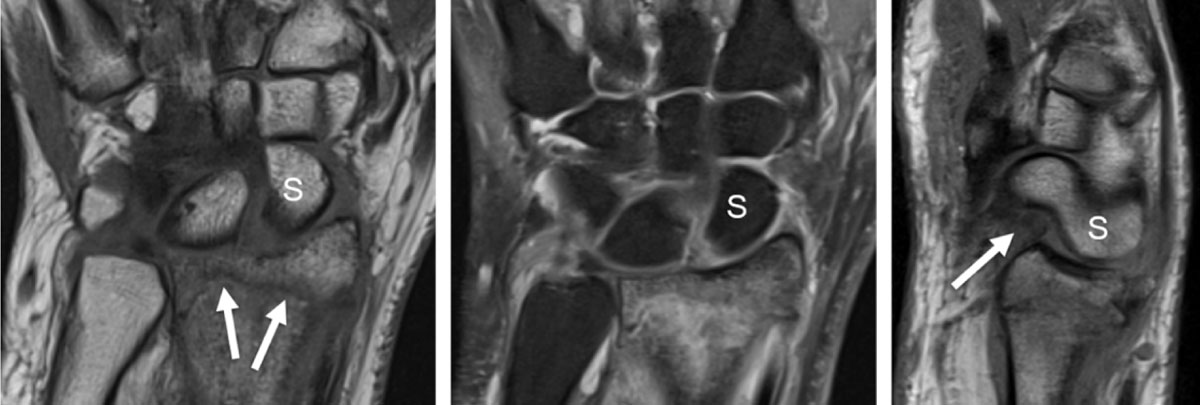

Figure 2

Distal radius fracture with associated intrinsic scapholunate (SL) and extrinsic palmar radiocarpal ligament rupture (RSC, radioscaphocapitate) detected by MRI. T1 coronal slice (a) shows the fracture line (arrows) and the increased SL space. Proton-density fat saturated coronal slice (b) demonstrates high signal surrounding bone marrow edema and increased signal of the SL space. Sagittal proton-density slice (c) detects a dorsal avulsion of the distal radius and a torn palmar RSC ligament (arrow) with rotatory subluxation of the scaphoid (S).